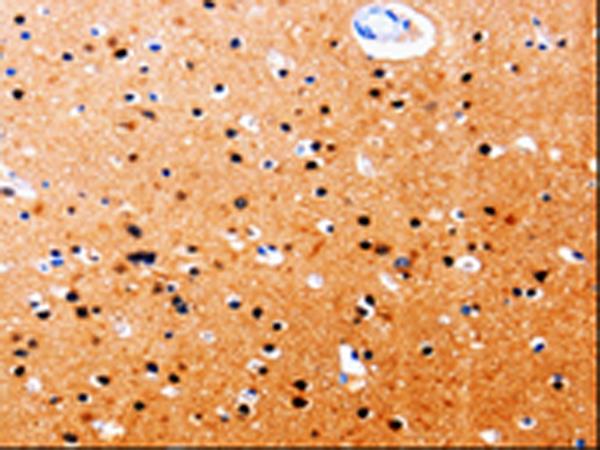

The image is immunohistochemistry of paraffin-embedded Human brain tissue using (GDI1 Antibody) at dilution 1/20. (Original magnification: ×200)